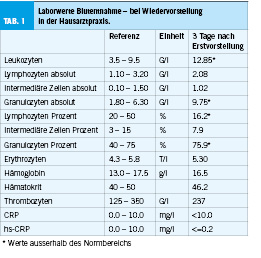

Im Labor (Tabelle 1) waren eine Leukozytose (12.85 G/l) sowie Granulozytose (9.75 G/l) zu sehen, bei normwertigem C-reaktivem Protein (CRP). Das restliche Blutbild war unauffällig (Abbildung 1).